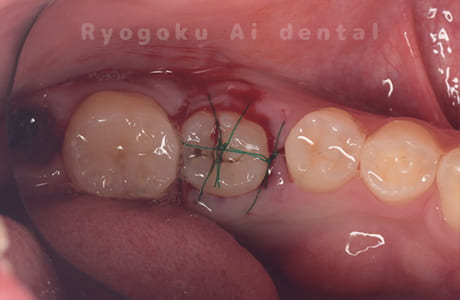

Case02

-

- 原因

- C4

- 治療期間

- 3ヶ月

- 治療内容

- 自家歯牙移植手術+マイクロエンド+ダイレクトボンディング

- 治療費用

- 220,000円

他院で虫歯が大きく、抜歯と判断され、インプラント手術を提案された患者様です。親知らずが残存していたため、自家歯牙移植手術を行いました。

<リスク・副作用>

治療後、痛みや違和感、出血、腫れなどが出る事があります。喫煙者、糖尿病などの方の場合、歯が生着しない場合があります。